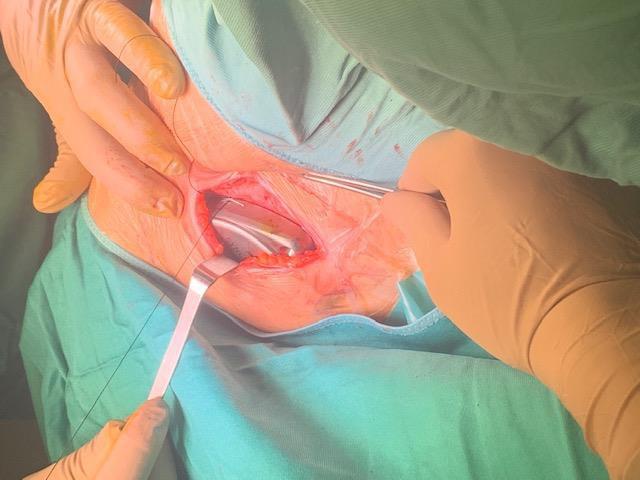

SDR involves surgically accessing the spinal cord (typically in the lumbosacral region, L2 to S1 or S2).The dorsal (sensory) nerve roots are carefully identified and then divided into smaller bundles called rootlets.

Adductor Longus L2, L3

Vastus Lateralis L3,L4

Tibialis Anterior L4, L5

Peroneus longus L5, S1

Gastrocnemius S1, S2

Abductor hallucis S1, S2

Sphincter S2